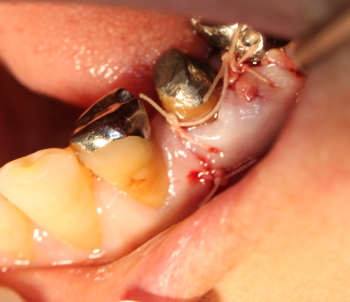

同部を剥離、掻爬